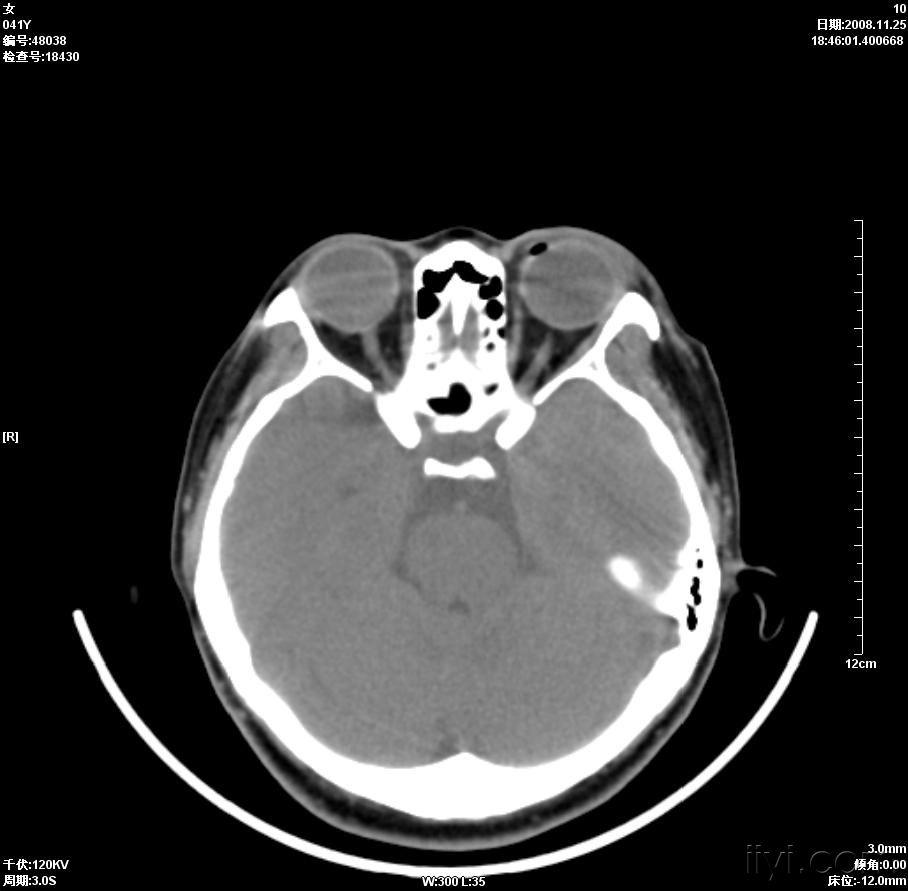

晶状体移位ct病例